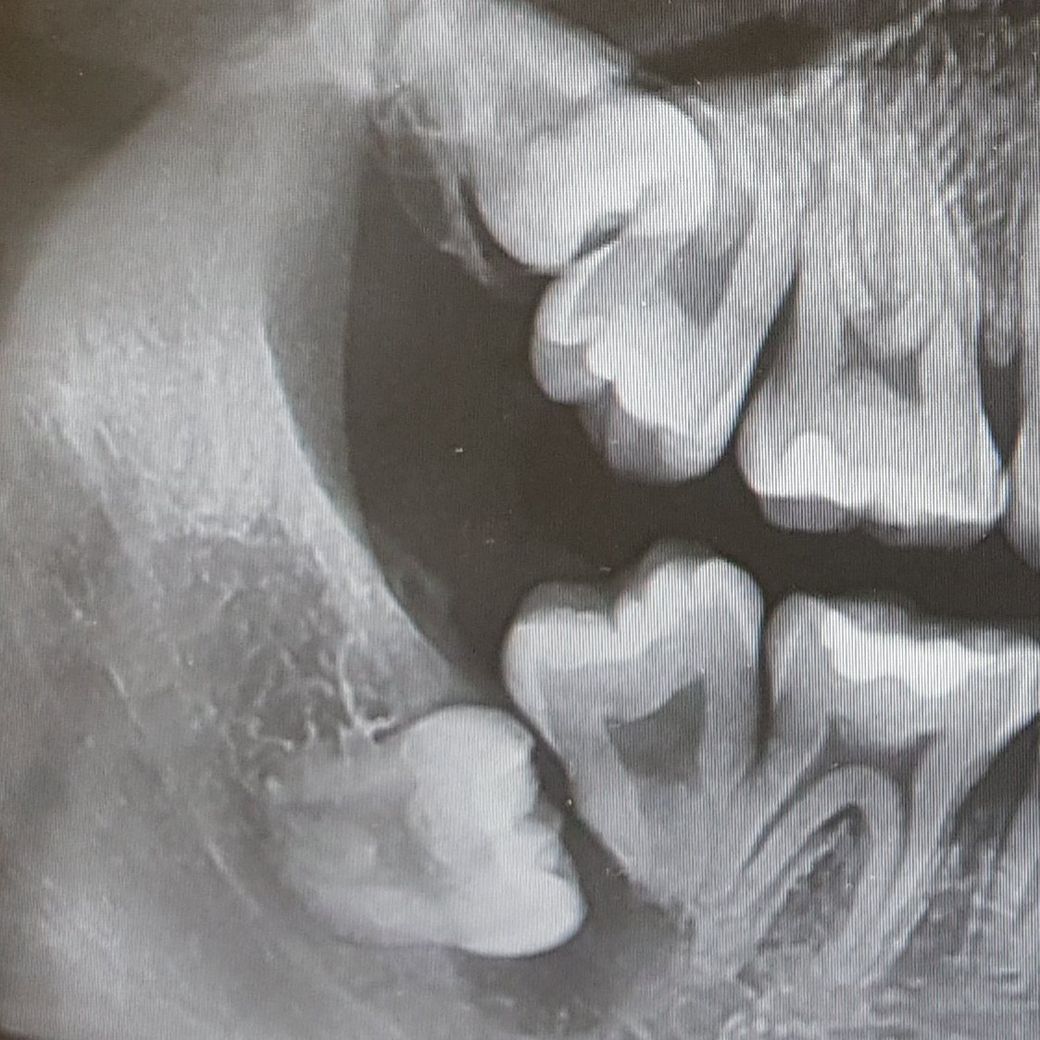

어느샌가 부터 찬 음식을 먹을때 이가 시려서 치과를 방문했더니 사진을 보시고는 사랑니, 어금니를 둘다 발치하고 임플란트를 해야한다고 해서 좀 더 규모가 있는 치과에 갔는데도 똑같이 말씀하셔서 심란해서 질문드립니다.

현재 파노라마 사진상에서 볼때, 사랑니와 그 앞의 제2대구치를 모두 발치하고나서 뼈가 회복될때까지 기다린 이후 임플란트를 하는 것이 가장 올바른 치료방법으로 보입니다.

현재 사진으로 보아서는 두 치아 모두 발치를 해야하며 심할 경우에는 사랑니 앞에 있는 어금니 2개 모두 발치해야할 수도 있어 보입니다. 질문자님이 말씀하시는 자연치로 인한 transplantation은 염증이 없다는 전제가 있어야 하지만 현재 사진은 염증이 매우 심합니다. 지속적으로 방치시 치조골이 계속해서 녹을 것으로 보이고 심한 경우 신경까지 침범할 수 있는 상황으로 보입니다.

사진으로 봤을 때 사랑니와 그 앞치아를 다 빼야하는 상황으로 보입니다.

사랑니가 어금니를 대체할 수 있는 상황이 아닌것으로 보입니다. 사랑니앞치아의 잇몸뼈가 너무 많이 녹아있기 때문입니다.

오른쪽 아래 사랑니와 어금니에 문제가 있습니다.

오른쪽 아래 사랑니의 염증으로 인하여 어금니 뒤쪽까지 염증이 번저 어금니 주위의 뼈가 녹아 없어져

어금니를 뽑지 않고는 대안이 없습니다. 두면 점점 뼈가 녹아 없어지니 가능한 빨리 사랑니와 어금니를 같이 뽑는 것이

좋습니다.

상태가 많이 안좋습니다. 이미 사랑니로 인한 염증때문인지 다른 치아낭때문인지 인접치가 거의 공중에 떠 있는상태이므로 발치를 하시는게 맞을것같습니다.